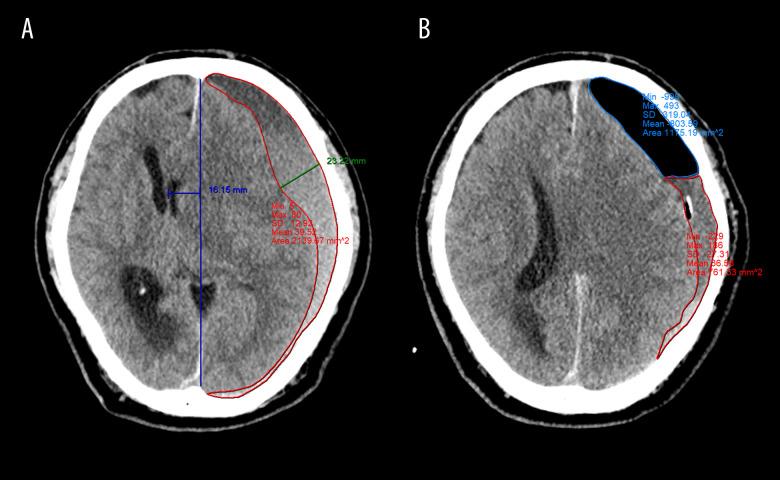

本单中心回顾性研究旨在比较 208 例单侧慢性硬脑膜下血肿(CSDH)患者在接受颅骨钻孔术(BHC)和血肿引流后 48 小时内和 48-5 天内的患者结局。

根据引流时间将患者分为两组:早期(1 或 2 天,n=100)和晚期(3-5 天,n=108)拔管。我们比较了两组的临床结局、复发率、复发时间和并发症。还对不同时间点(术后、拔管当天和术后第 7 天)的 CT 参数进行定量分析,以比较影像学结果。

两组的临床结局和复发率相似。虽然晚期拔除组的总引流量明显更大(P<.001),但通过所有时间序列,我们发现两组的影像学结果没有显著差异。